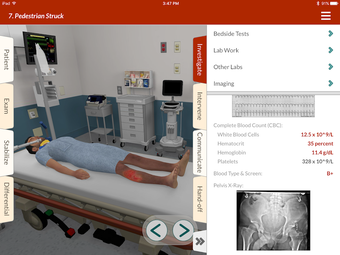

Full Code - Emergency Medicine Simulation è un'applicazione Android sviluppata da Minerva Medical Simulation Inc. È una versione completa con licenza di un'applicazione di stile di vita che rientra nella sottocategoria medica. È un'applicazione di simulazione intuitiva, mobile-first che offre oltre 160 casi virtuali realistici e un'interfaccia coinvolgente simile a un gioco, preferita dai professionisti medici di tutto il mondo. L'applicazione è progettata per aiutare gli studenti e i professionisti medici a acquisire fiducia nel trattamento di casi complessi e offre 0,5 crediti AMA PRA Categoria 1™ per ogni caso Full Code giocato con Full Code Pro+CME.

L'applicazione consente agli utenti di esercitarsi in diagnosi cliniche rare e rischiose in un ambiente sicuro in modo da poter affrontare casi complessi del mondo reale con fiducia. Con oltre 160 casi in 31 specialità, Full Code consente di esercitarsi in simulazioni mediche on-demand ogni volta che si ha una pausa, ovunque ci si trovi. L'applicazione è ottimizzata per la portabilità e l'accessibilità ed è disponibile su qualsiasi dispositivo mobile, desktop o tablet. Full Code è accreditato attraverso l'ACCME e, con la sua sottoscrizione PRO+CME, gli utenti possono completare i loro requisiti di formazione medica continua (CME) con sfide di simulazione flessibili e piacevoli. È un'applicazione eccellente per i professionisti medici che vogliono migliorare le proprie competenze e acquisire fiducia nel gestire casi complessi.